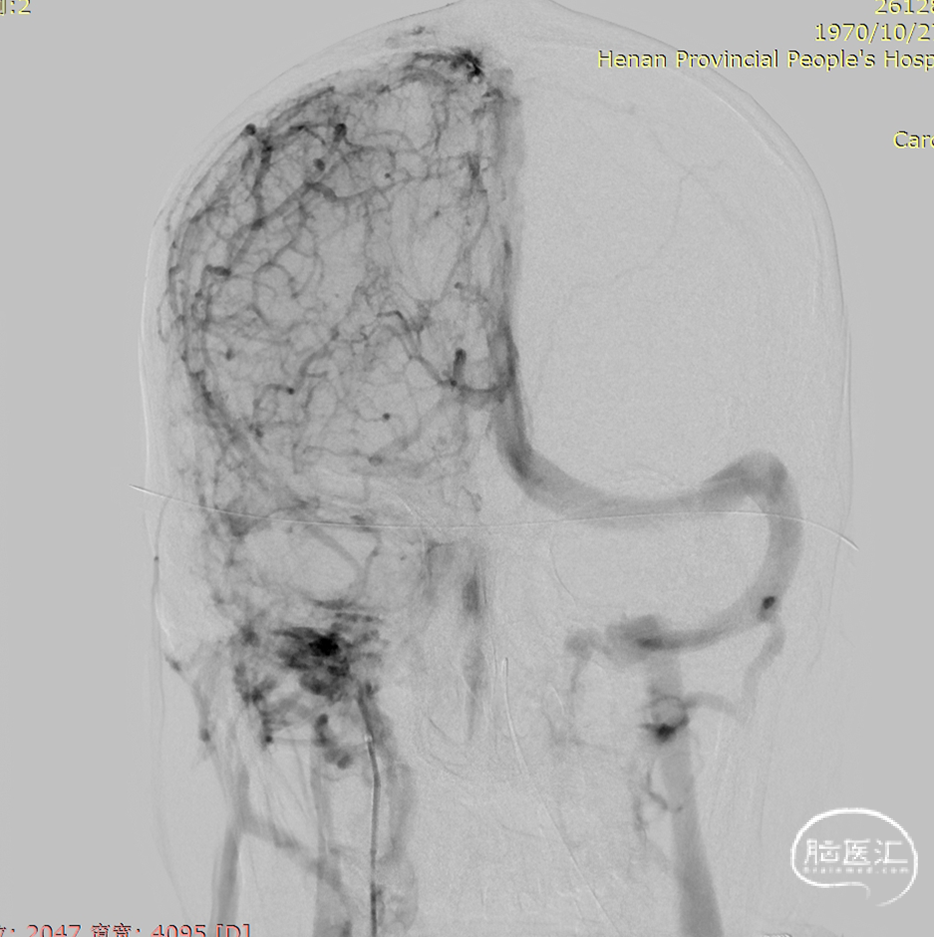

术前DSA静脉期可见上矢状窦及右侧横乙窦充盈缺损。

术后造影显示上矢状窦较前明显改善。

术前上矢状窦闭塞

术后上矢状窦再通